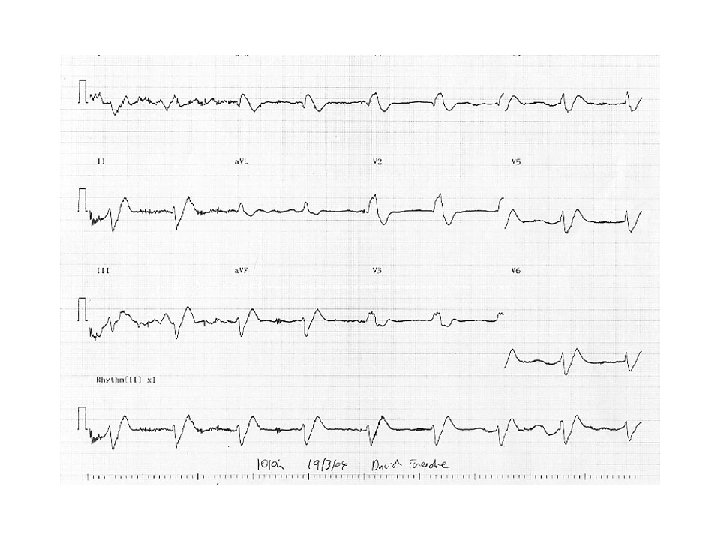

6 E Which of the following is correct concerning hyperkalaemia? • • A It may be caused by beta blockers B It may be caused by paracetamol C It may be caused by liquorice excess D It can be corrected by IV calcium gluconate • E Causes ventricular tachycardia and fibrillation

6 E Which of the following is correct concerning hyperkalaemia? • • A It may be caused by beta blockers B It may be caused by paracetamol C It may be caused by liquorice excess D It can be corrected by IV calcium gluconate • E Causes ventricular tachycardia and fibrillation

6 E Which of the following is correct concerning hyperkalaemia? • • A It may be caused by beta blockers B It may be caused by paracetamol C It may be caused by liquorice excess D It can be corrected by IV calcium gluconate • E Causes ventricular tachycardia and fibrillation

6 E Which of the following is correct concerning hyperkalaemia? • • A It may be caused by beta blockers B It may be caused by paracetamol C It may be caused by liquorice excess D It can be corrected by IV calcium gluconate • E Causes ventricular tachycardia and fibrillation

Hyperkalaemia • Aetiology • Main causes begin with A - ARF, Addisons, Acidosis, Artefact, ACEI, ARBs, Aldosterone antagonists, anti-inflammatories eg NSAIDs, also beta blockers but not paracetamol (no effect) or liquorice (hypokalaemic alkalosis) • Presentation • Peaked T waves followed by loss of P wave, broadening of QRS complex (may mimic LBBB) then bradycardia leading to asystole or VF (but not VT) • Management • Depends on level of K, likelihood it will rise further (always more dangerous in ARF than CRF) and ECG changes

Hyperkalaemia • Aetiology • Main causes begin with A - ARF, Addisons, Acidosis, Artefact, ACEI, ARBs, Aldosterone antagonists, anti-inflammatories eg NSAIDs, also beta blockers but not paracetamol (no effect) or liquorice (hypokalaemic alkalosis) • Presentation • Peaked T waves followed by loss of P wave, broadening of QRS complex (may mimic LBBB) then bradycardia leading to asystole or VF (but not VT) • Management • Depends on level of K, likelihood it will rise further (always more dangerous in ARF than CRF) and ECG changes